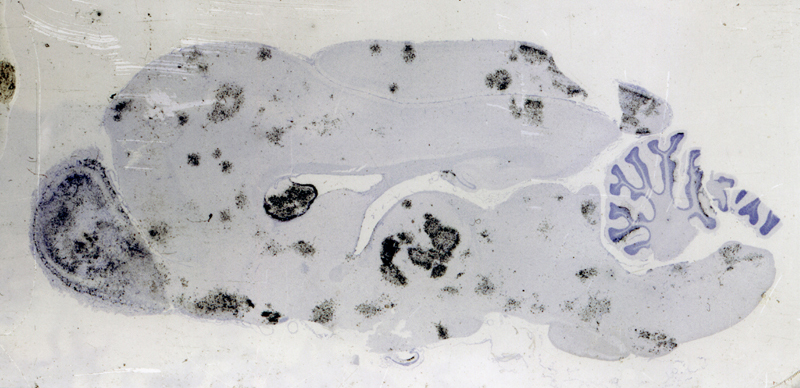

How would the hypothetical virus reach the CNS and propagate between hosts? While many pathways could be used, aerosol transmission is the most effective means of spreading between high density host populations (Figure 6). Additionally, for entirely mysterious reasons, aerosol dissemination is highly effective at transferring virus to the brain. Viruses that normally are limited to peripheral infections, when aerosolized, lead to severe pan-CNS infection (e.g., Rift Valley fever virus, Figure 7).

Figure 6A. In situ hybridization autoradiography (black grains) for Influenza A in the brain of a ferret 8 days after aerosol exposure to H5N1. Numerous foci throughout the brain demonstrate abundant flu infected cells.

Figure 6B. Higher power image showing regions of intense neuroglial infection.

Figure 7. When Rift Valley fever virus (RVFV) is transmitted by mosquito bite, infection does not cause an encephalitis. However, when delivered as an aerosol, RVFV causes a global encephalitis. In situ hybridization autoradiography (black grains) for RVFV in the brain of a mouse 7 days after aerosol exposure to RVFV. Essentially all of the neurons are infected.